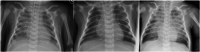

Severe acute respiratory syndrome coronavirus 2 (SARS-CoV-2), the etiological agent of coronavirus disease 2019 (COVID-19), may manifest as a life-threatening respiratory infection with systemic complications. Clinical manifestations among children are generally less severe than those seen in adults, but critical cases have increasingly been reported in infants less than 1 year of age. We report a severe case of neonatal COVID-19 requiring intensive care and mechanical ventilation, further complicated by a multidrug-resistant Enterobacter asburiae super-infection. Chest X-rays, lung ultrasound, and chest computed tomography revealed extensive interstitial pneumonia with multiple consolidations, associated with persistent increased work of breathing and feeding difficulties. SARS-CoV-2 RNA was detected in respiratory specimens and stools, but not in other biological samples, with a rapid clearance in stools. Serological tests demonstrated a specific SARS-CoV-2 antibody response mounted by the neonate and sustained over time. The therapeutic approach included the use of enoxaparin and steroids which may have contributed to the bacterial complication, underlying the challenges in managing neonatal COVID-19, where the balance between viral replication and immunomodulation maybe even more challenging than in older ages.